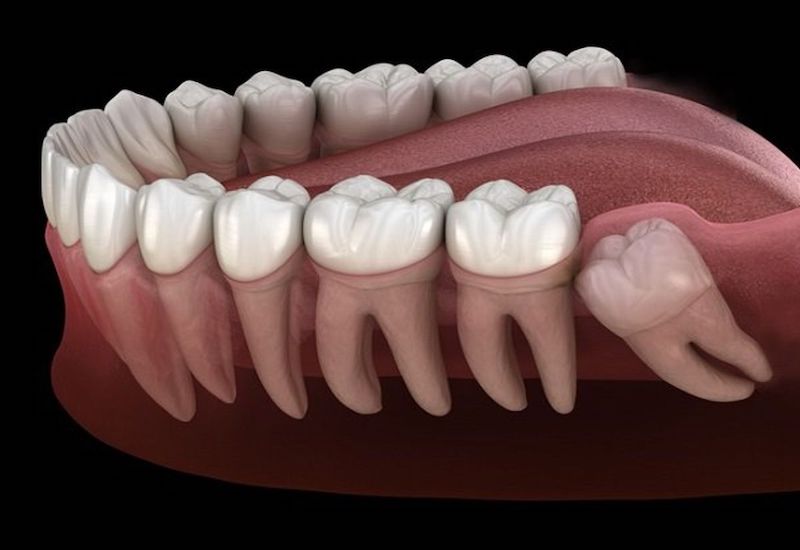

Lý do mọc lệch: Sự tiến hóa của loài người khiến xương hàm ngày càng thu nhỏ lại để phù hợp với chế độ ăn uống mềm hơn. Tuy nhiên, số lượng răng vẫn giữ nguyên là 32 chiếc. Chính sự mất cân đối này dẫn đến tình trạng không đủ chỗ trống cho răng khôn mọc thẳng. Khi không có không gian, răng khôn buộc phải tìm đường khác để trồi lên, dẫn đến việc mọc xiên, mọc ngang hoặc thậm chí là mọc ngầm hoàn toàn trong xương hàm.

Các kiểu mọc lệch phổ biến: Tùy vào vị trí và hướng của mầm răng, răng khôn mọc lệch có thể chia thành nhiều dạng khác nhau:

Mọc lệch gần: Răng khôn nghiêng về phía răng số 7 bên cạnh một góc khoảng 45 độ, đâm trực tiếp vào chân răng hoặc thân răng số 7.

Mọc lệch xa: Răng khôn nghiêng về phía sau, hướng về phía cành cao xương hàm dưới hoặc xoang hàm trên.

Mọc lệch ngang: Răng khôn nằm ngang 90 độ so với các răng khác, thường bị kẹt hoàn toàn dưới nướu hoặc đâm ngang vào răng số 7.

Mọc ngầm: Răng nằm hoàn toàn trong xương hàm và bị nướu che phủ, chỉ có thể phát hiện thông qua phim chụp X quang.